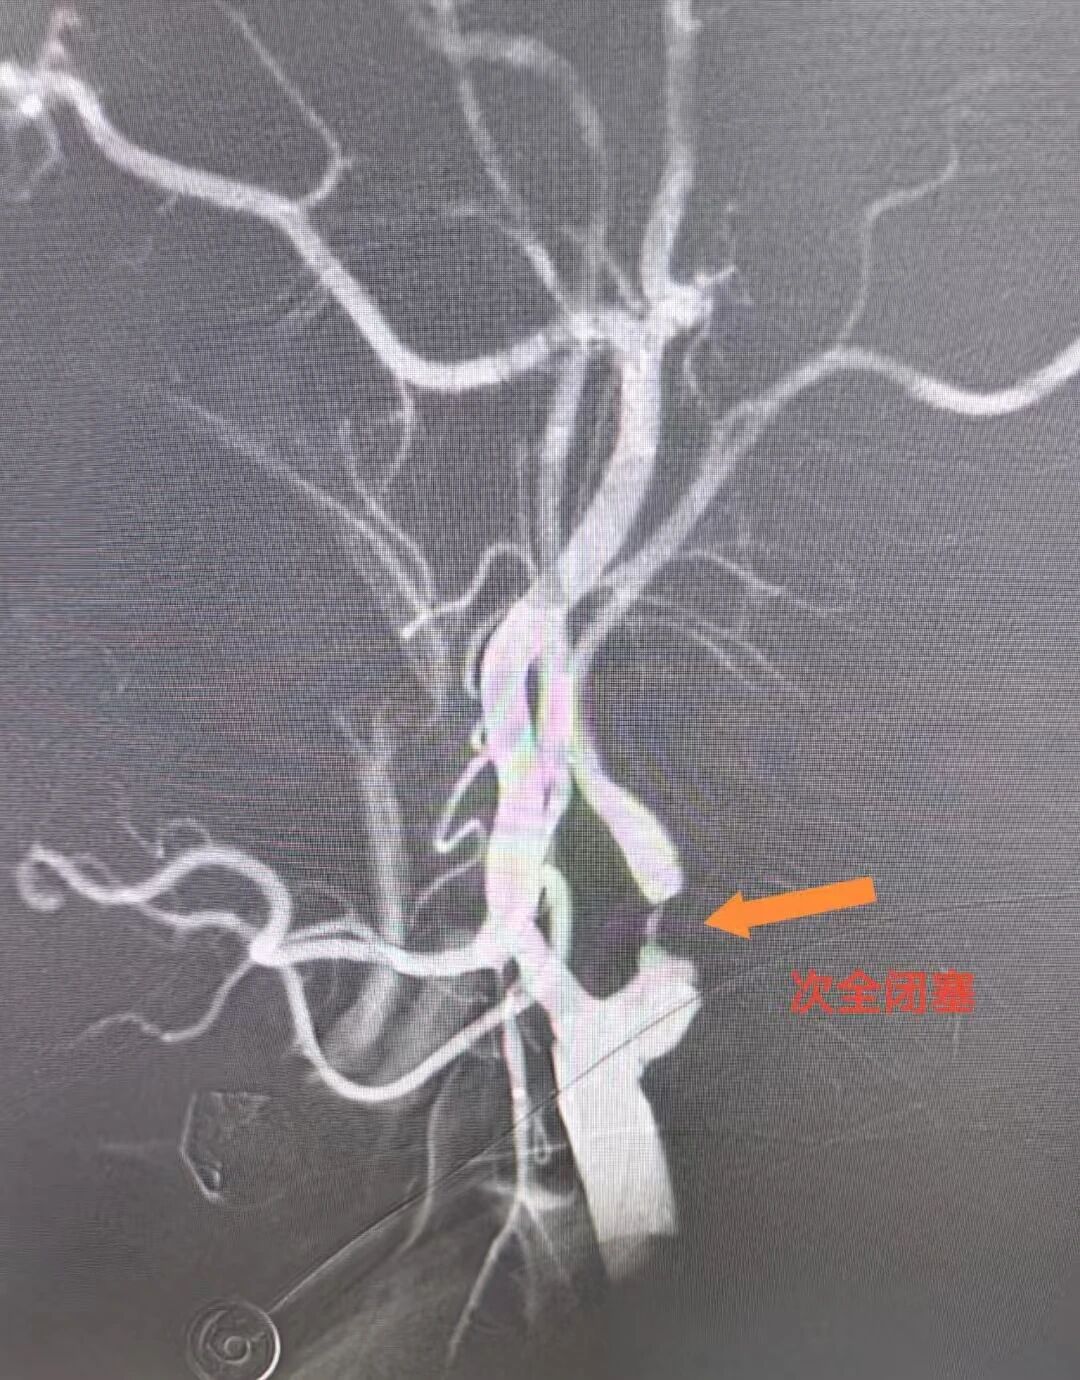

心脏问题刚解决,脑部危机便接踵而至。医疗团队迅速为罗先生实施脑动脉造影,结果显示其右侧颈内动脉近段狭窄达99%。然而心脏术后需维持稍高血压保障心功能,颈动脉支架手术却要求严控血压以规避脑出血风险——两种治疗需求如同天平的两端,在罗先生体内形成了棘手的治疗矛盾。手术团队经过反复研讨、全面评估,与家属进行了充分沟通,决定暂缓脑部手术,给予患者充分的恢复时间,待身体条件达到最佳状态后,再实施颈动脉支架植入手术。

同时,王和平教授紧急到院,带领诊疗团队采用股动脉穿刺微创通路,在DSA引导下精准植入支架,40分钟内解除颈动脉闭塞,造影显示颈动脉血流恢复通畅,术后次日患者即可下床活动。

DSA显示罗先生颈动脉闭塞